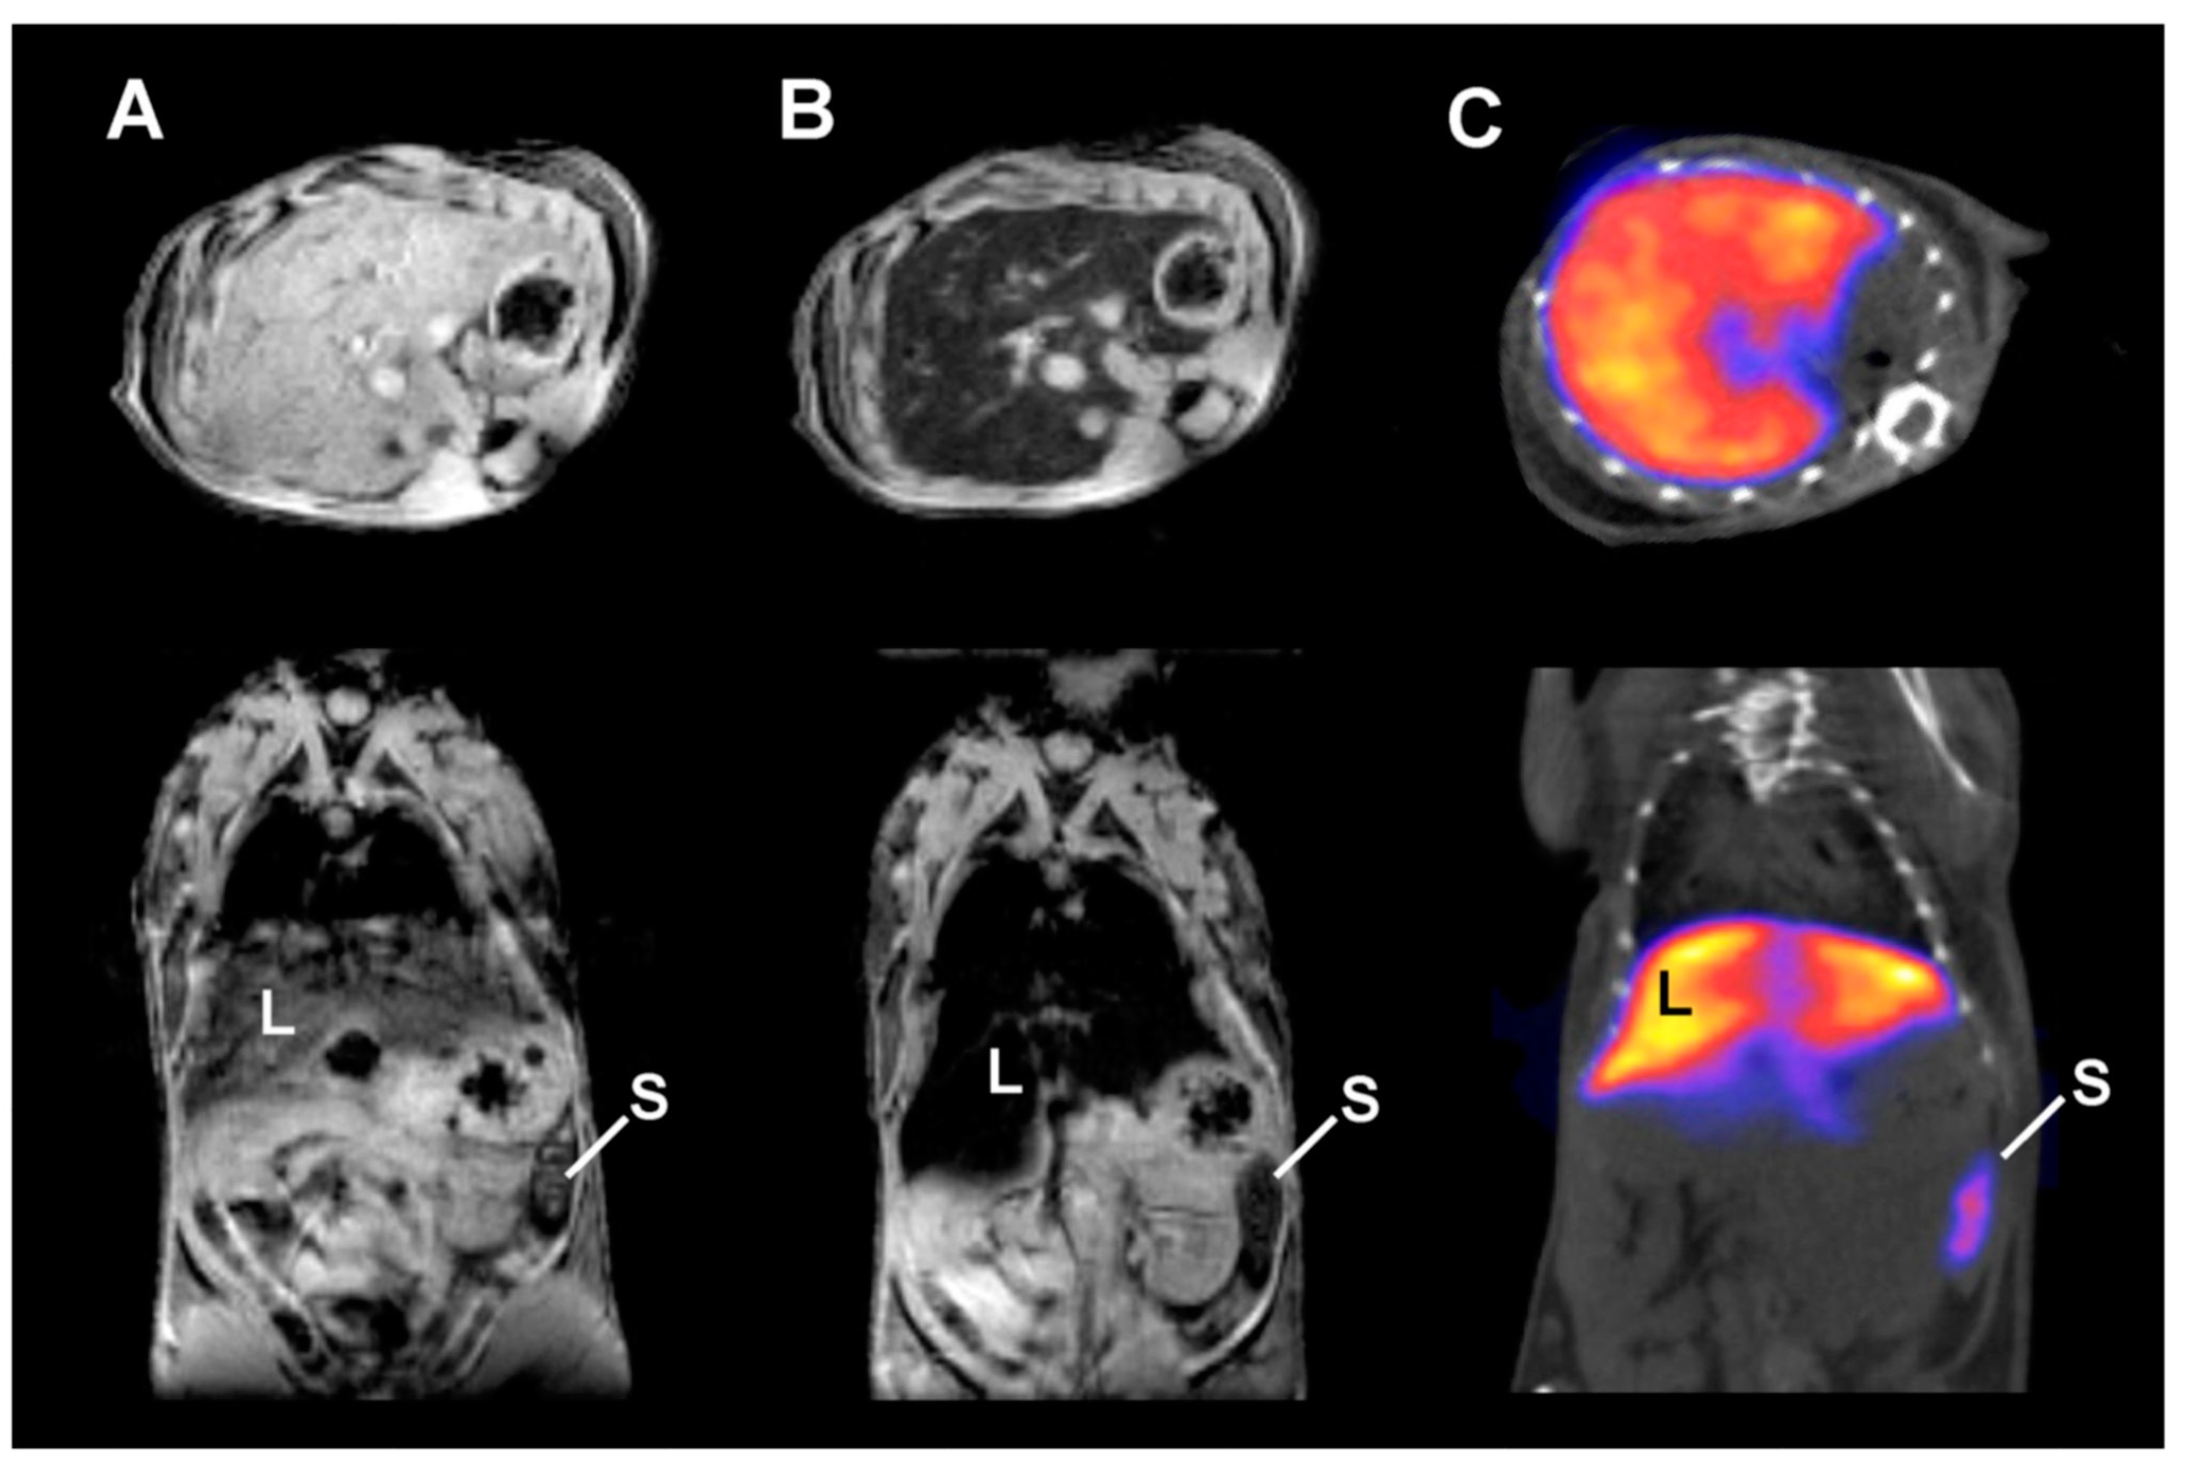

- Glaus, C.; Rossin, R.; Welch, M.J.; Bao, G. In vivo evaluation of 64Cu-labeled Magnetic Nanoparticles as a Dual-Modality PET/MR Imaging Agent. Bioconjug. Chem. 2010, 21, 715–722. [Google Scholar] [CrossRef]

- Karageorgou, M.A.; Vranješ-Đurić, S.; Radović, M.; Lyberopoulou, A.; Antić, B.; Rouchota, M.; Gazouli, M.; Loudos, G.; Xanthopoulos, S.; Sideratou, Z.; et al. Gallium-68 Labeled Iron Oxide Nanoparticles Coated with 2,3-Dicarboxypropane-1,1-diphosphonic Acid as a Potential PET/MR Imaging Agent: A Proof-of-Concept Study. Contrast Media Mol. Imaging 2017, 2017, 6951240. [Google Scholar] [CrossRef]

- Thorek, D.L.J.; Ulmert, D.; Diop, N.-F.M.; Lupu, M.E.; Doran, M.G.; Huang, R.; Abou, D.; Larson, S.M.; Grimm, J. Non-invasive mapping of deep-tissue lymph nodes in live animals using a multimodal PET/MRI nanoparticle. Nat. Commun. 2014, 5, 3097. [Google Scholar] [CrossRef]